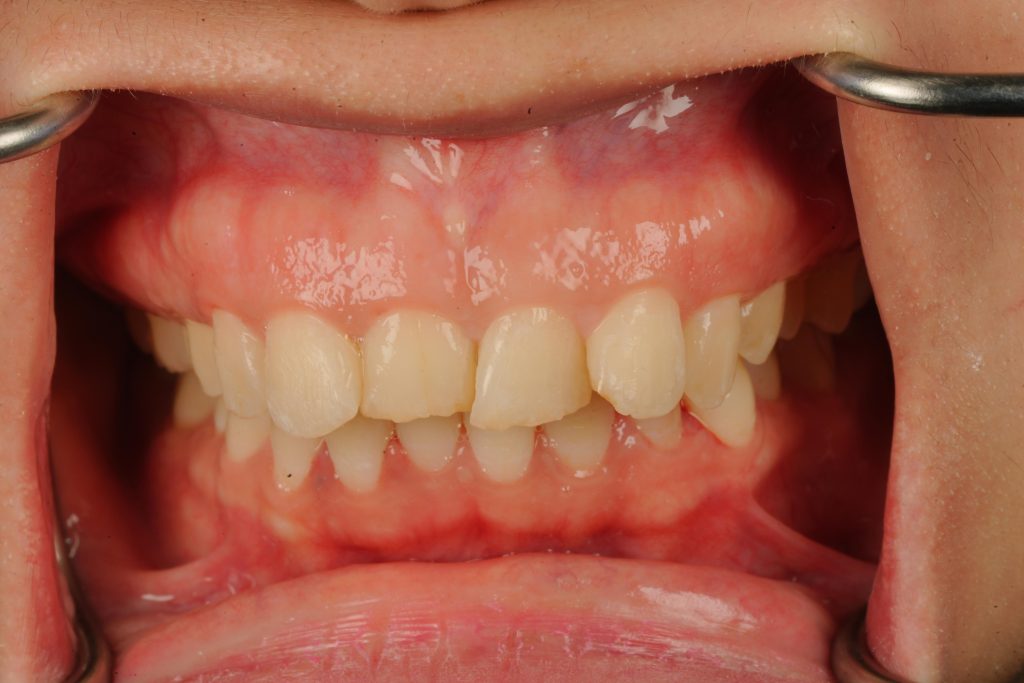

The patient presented with generalized discoloration, uneven incisal edges, and midline asymmetry (Fig 1). A Digital Smile Design (DSD) was created to analyze facial proportions and establish ideal tooth length-to-width ratios. Mock-ups were printed and tried intra-orally for patient approval before any tooth modification.

The result delivered a balanced, natural smile with enhanced harmony, translucency, and ideal gingival zenith alignment (Fig 6). The patient’s confidence and facial esthetics were significantly improved while maintaining tooth vitality and enamel integrity.